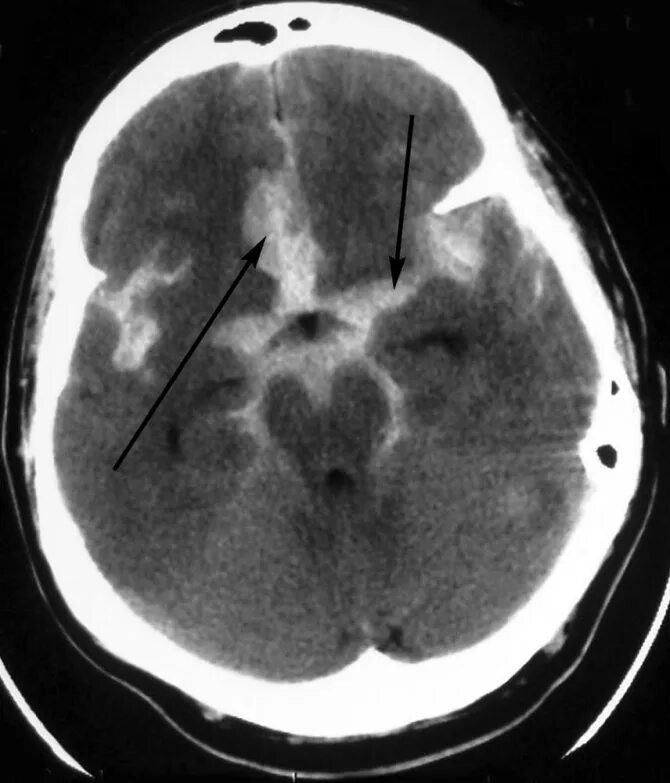

Аневризма головного мозга на кт